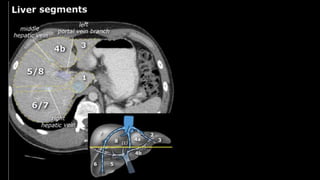

•Liver • A normalliver enhances homogeneously (irrespective of the scan phase). The liver receives about 80% of its blood through the portal vein (= nutrient-rich blood from the intestines). The remaining 20% is supplied by the hepatic artery. y is present, it is important to document its location. This may be crucial to any surgical options. Using the Couinaud classification, the liver is subdivided into eight individually functioning segments. Each segment has its own afferent hepatic artery and portal vein, and efferent hepatic vein and efferent bile ducts